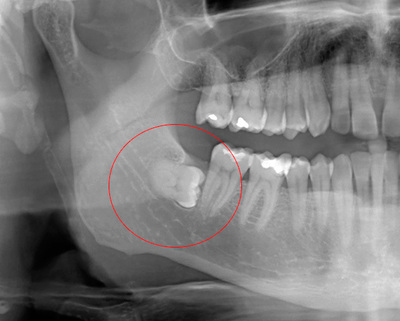

Исполнилось мне 23 годика и вот, в мою ротовую полость постучались они - зубы мудрости. Один из них вёл себя особенно отвратительно, как сосед алкоголик в коммуналке. Рос в щеку, царапал язык, двигал соседей и постоянно болел. После посещения стоматолога было принято решение - выселять его к черту. Я собрала волю в кулак и записалась к лучшему в городе хирургу. Отзывы о нём были неоднозначные: как спец - он просто высший класс, но вот в общении и подходе к клиентам - крайне специфичен. Ну да, не детей с ним крестить, и я выбрала именно его, исходя из профессиональных качеств.

- Ну заходи, раз пришла! - доносится бас из-за двери. И я вхожу. Сажусь и продолжаю дрожать, понимая что всё... Отдаю направления, снимки, а в голове только мысль: "Пропала я!"